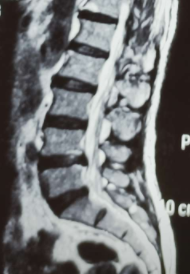

该患者因腰痛伴左下肢麻木1年,加重半年。因保守治疗效果欠佳,严重影响正常生活。入院后经查体:患者左小腿外侧、足背刺痛觉减退,左下肢直腿抬高40°阳性。左踇趾背伸力减弱。

经专家会诊,决定对该患者实施微创经椎间孔入路腰椎椎体间融合术(MIS-TLIF),这也是我院首例微创经椎间孔入路腰椎椎体间融合术(MIS-TLIF)。手术过程顺利,术后患者生命体征趋于平稳、精神状态明显好转,术后3天就能拔管下地。